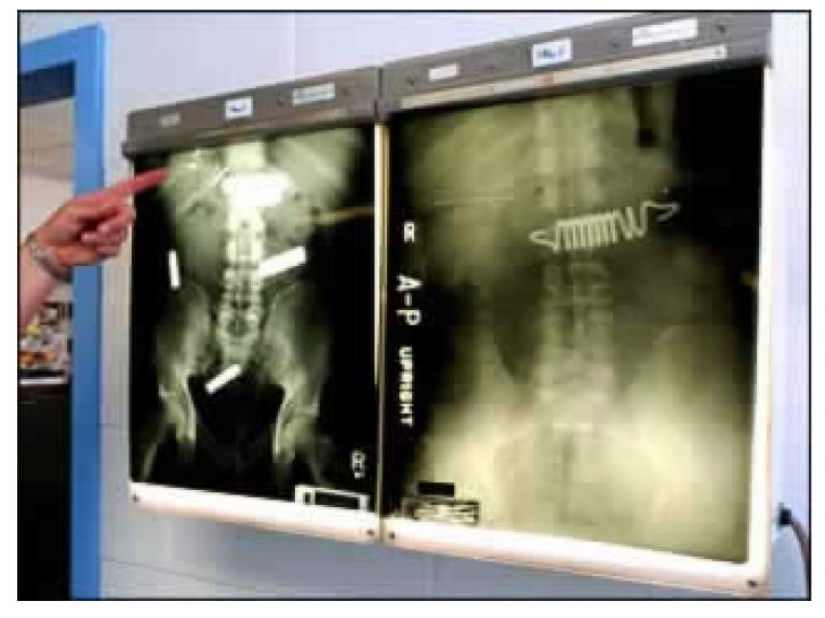

Some inmates are willing to swallow anything just to get out of prison, for example, in the hospital — even the springs from the mattress.